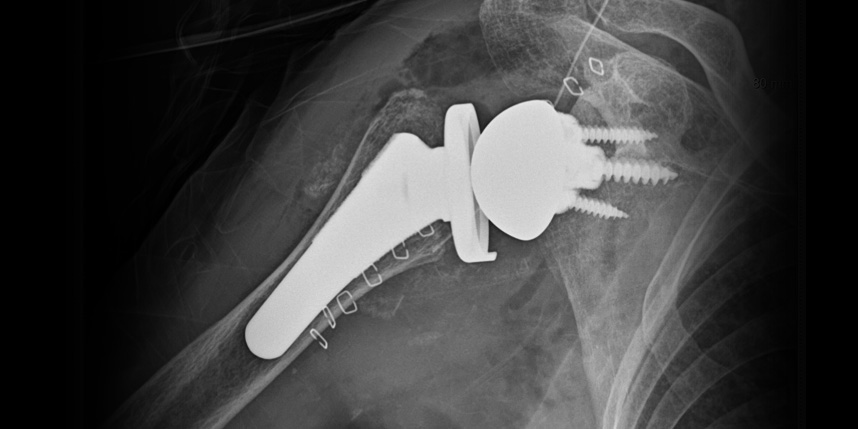

삼하게 망가져 거의 기능이 없는 관절을 제거한 후 특수하게 제작된 인공관절을 삽입하는 수술

비수술 치료에도 호전이 없는 경도의 관절염에서 시행합니다.

역행성 인공관절 전치환술

역행성 인공관절 진치환술

(회전근개 심한 파열 및 관절염 진행)